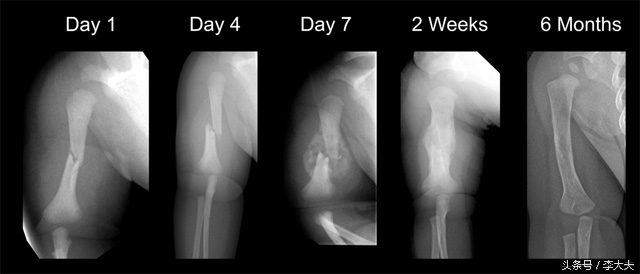

骨折愈合X线片表现

这是骨折的II期愈合情况,I期愈合最理想,但是临床较难实现,这里不做扩展解释。